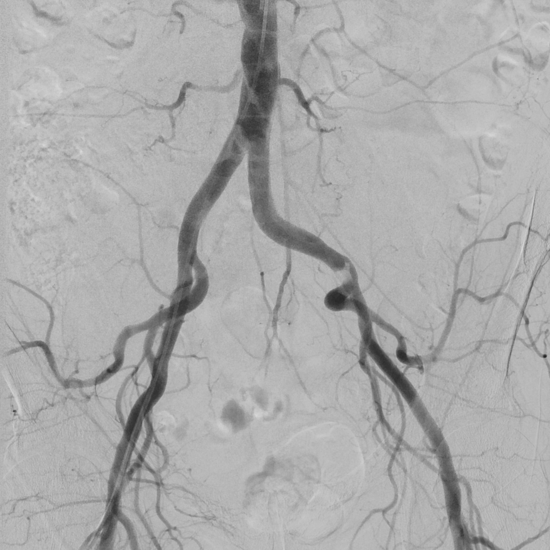

Digitale Subtraktionsangiografie:

Diese Untersuchungsmethode wird nur noch im Rahmen der Therapie oder bei unklaren durch andere Methoden erhobenen Befunden durchgeführt. Dazu wird nach Verabreichung eines Schmerzmittels eine Punktion der Oberschenkel- oder Armarterie durchgeführt und ein dünner Katheter in das Gefäß vorgeschoben. Über diesen Katheter erfolgt eine Kontrastmittelinjektion zur Darstellung der Gefäße. Ein spezielles Röntgengerät macht während der Injektion Aufnahmeserien des Blutflusses in dem zu untersuchenden Gefäßgebiet.